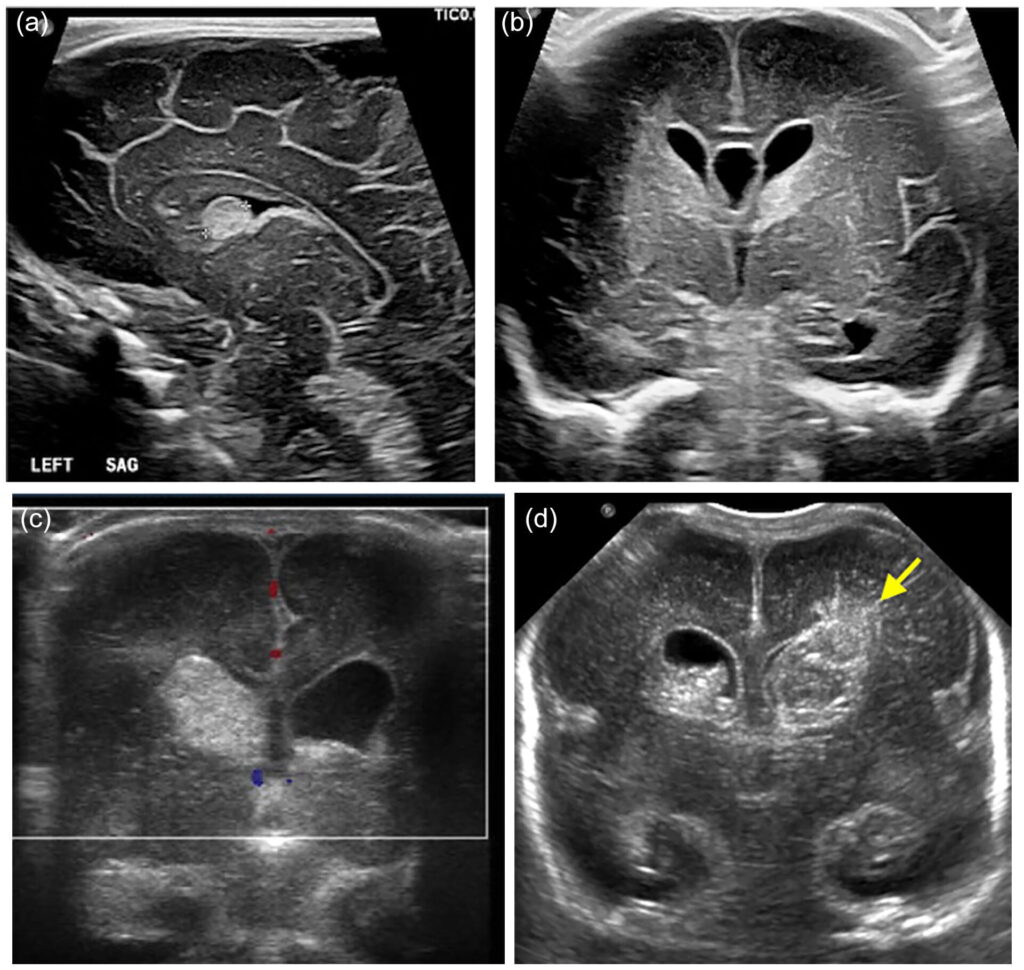

A Pediatric Neurosonogram is a safe, ultrasound-based scan used to examine a baby’s brain. It is mainly performed in newborns and infants, where the soft spot on the head (fontanelle) allows sound waves to pass through and create detailed images of the brain structures.

A special ultrasound probe is gently placed over the fontanelle (soft spot) on the baby’s head

Sound waves create real-time images of the brain